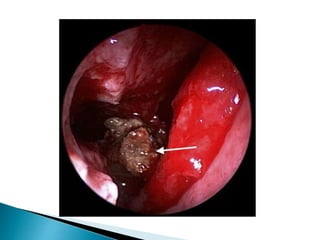

 Initial or a cursory nasal examination may not reveal

anything significant.

Therefore, it is always advisable to decongest the

nose and perform nasal endoscopy. A discolouration

of the nasal mucosa and serosanguineous discharge

should be looked for.

 Crusting, whitish discolouration (due to tissue

ischemia) or black discolouration with eschar

formation (due to tissue necrosis) may be present .

 There could also be granulation or ulceration of the

nasal mucosa.These changes have been most

commonly found to occur on the middle turbinate,

followed by the septum, palate and inferior turbinate.